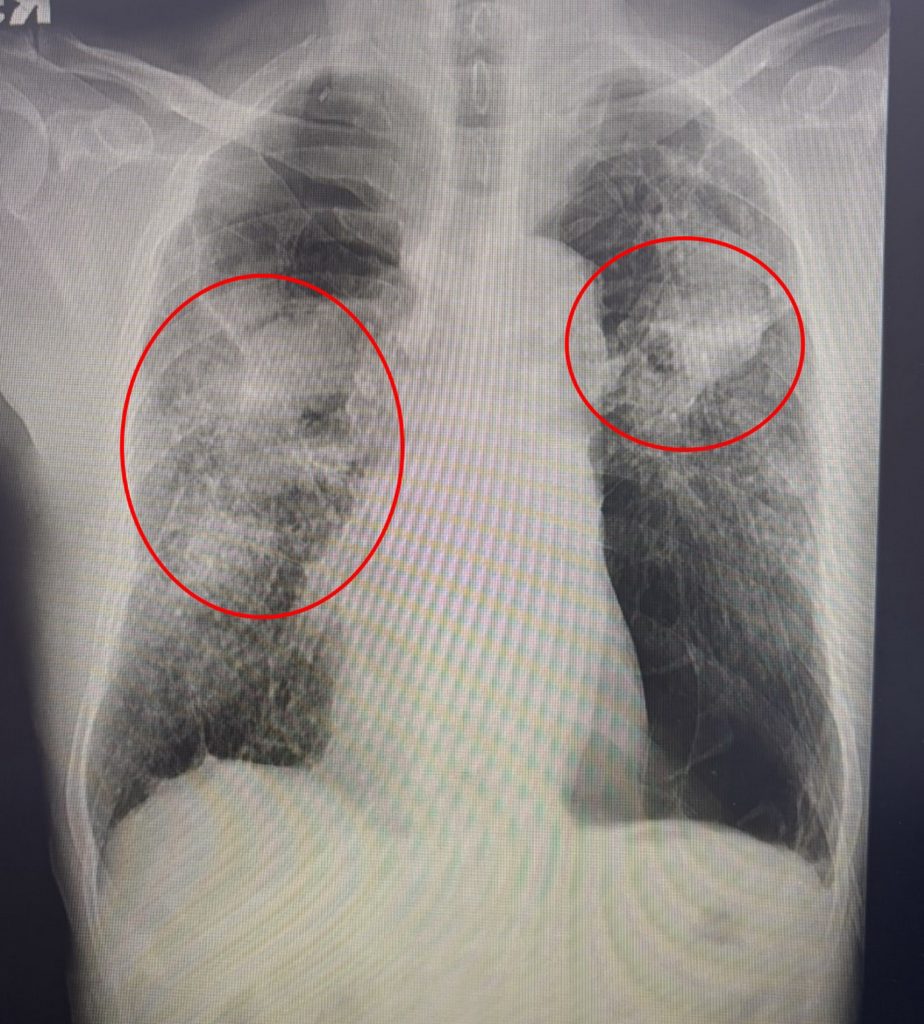

70多歲男子有慢性阻塞性肺病及心律不整,日前他在家發燒,喘到連走幾步都困難,緊急送醫確診為A型流感,併發肺炎,胸部X光片更顯示大片白霧,呼吸功能急遽惡化,住院2週治療才穩定出院。

光田綜合醫院胸腔內科醫師簡格凌表示,70多歲男子因慢性阻塞性肺病,導致原本肺功能就差,此次流感使呼吸道症狀嚴重,須依靠氧氣面罩維持呼吸。雖然投予抗病毒藥物與抗生素,仍因併發症多,恢復相當緩慢,一般流感多住院1週,但老翁住院2週後才穩定出院。